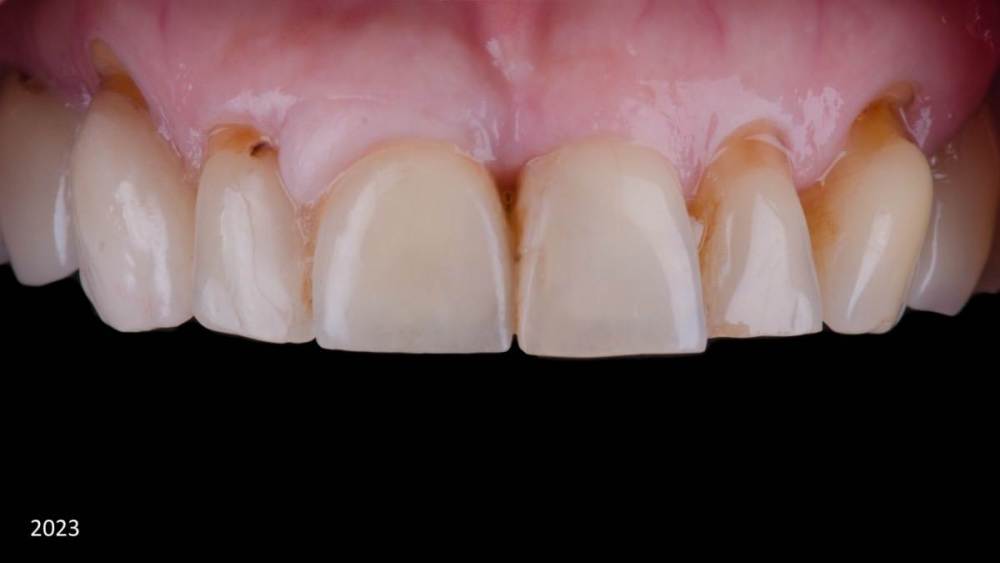

Владмир Опубликовано 20 марта, 2023 Автор Поделиться Опубликовано 20 марта, 2023 Здравствуйте коллеги. Работе 10 лет. Фото начальных этапов добавил 7 1 2 Ссылка на комментарий